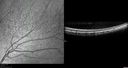

12 year old female She went last December for her regular checkup and spots were noted on the retina in the periphery. Her vision is fine and there is no family history of retinal disease. She has difficulty seeing at night and finding her way in a dark theater. VA OD: Dcc20/20-1 NccJ1+ VA OS: Dcc20/20 NccJ1+

Fundus Albipunctatusvista 962 veces12 year old female with normal vision. She has 4 siblings all of whom have either white spots or spots on IR. Genetic testing by parents was deferred.00000